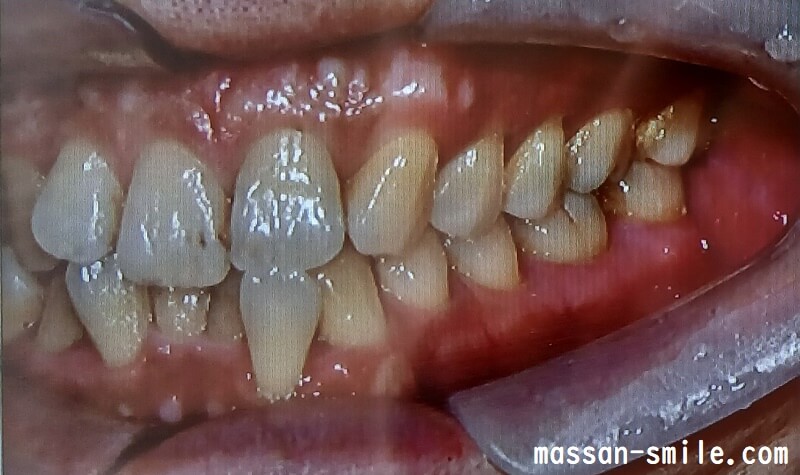

画像を見てもらえれば(↓)と思いますが、私の場合、もともと上の前歯が1本足りないです。

下の前歯は、本数は正常ですが、入りきらなくてガタガタになっています。

- 歯列矯正前の歯並び

そしてその状態から、前歯上下の歯並びを整えていくという方法でした。